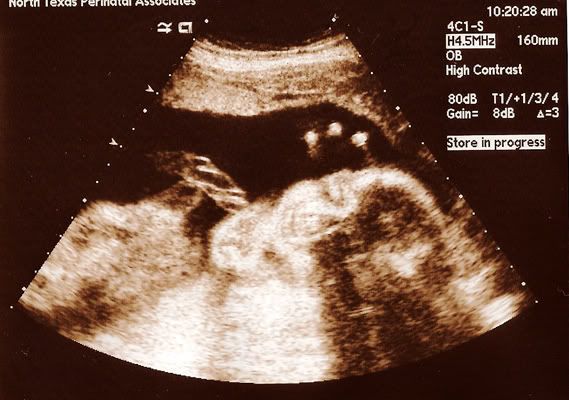

今天又去照超声波了,还看到宝宝的脸哦!看到他的脸的那一刻,我流眼泪哦。。pai seh,不知道为什么眼泪就不由自主流下来。。

医生说,宝宝看起来一切正常,健康。。现在的宝宝已经有2磅重了哦!

看到吗?他只给我们看他半边脸。。真是"号练"哦! |

看到了看到了!

看到boy boy在笑哦~~一定在发美梦了

我觉得他很像TS叻! 看来他好梦整甜呢! |

真的像是在笑呢!我发现怀孕后情绪波动,加上泪腺发达,一点点地感动都可以让我流泪~所以学姐不需要paiseh啦! |